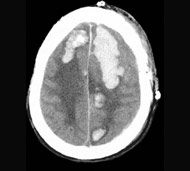

У результаті травми голови може виникнути cубдуральна, епідуральна або внутрішньомозкова гематома.

Субдуральна гематома

Ця гематома розвивається при розриві кровоносних судин - зазвичай вен - між головним мозком і твердою мозковою оболонкою (зовнішньою з трьох оболонок, що покривають головний мозок). Кров, що виливається, утворює гематому, яка здавлює тканини головного мозку. Якщо гематома збільшується, відбувається прогресивне згасання свідомості, що може призвести до смерті.

Епідуральна гематома

Цю гематому також називають екстрадуральною, вона розвивається при розриві кровоносної судини - зазвичай артерії - між зовнішньою поверхнею твердої мозкової оболонки і черепом. Часто пошкодження кровоносної судини відбувається внаслідок перелому черепа. Кров витікає між твердою мозковою оболонкою і черепом, утворює масу, яка здавлює тканини головного мозку.

Внутрішньомозкова гематома

Цей тип гематоми розвивається при проникненні крові в головний мозок. Після травми голови можуть виникнути численні важкі внутрішньомозкові гематоми. Травма, яка призвела до появи такої гематоми, часто викликає ураження з пошкодженням білої речовини. Такі пошкодження розвиваються після того, як травма буквально розриває нейрити в білій речовині головного мозку. Нейрити - це з'єднання, що передають електричні імпульси або повідомлення від нейронів головного мозку до решти частин організму. При втраті даного з'єднання можуть з'явитися серйозні пошкодження головного мозку, тому що нейрони більше не можуть взаємодіяти.

Діагностування гематоми може бути складним. Однак лікарі в основному припускають, що прогресуюча втрата свідомості після травми голови викликається крововиливом в череп, якщо не доведено інше. Кращий спосіб визначити локалізацію і розмір гематоми - це візуалізація.

- комп'ютерна томографія (КТ). Для отримання зрізів КТ застосовується сучасний рентген-апарат, підключений до комп'ютера для виконання детальних зображень головного мозку.